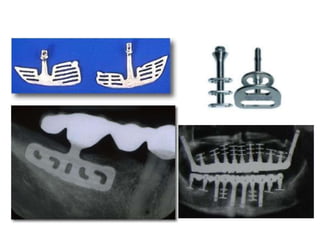

• Implant dạng bản

• Implant dạng đĩa

• Implant dạng chân răng (root form)

–Implant một khối

–Implant hai khối

Implant • Implant dạngbản • Implant dạng đĩa • Implant dạng chân răng (root form) –Implant một khối –Implant hai khối • Trụ chuyển implant (Abutment mount) • Vít đậy (Cover screw)